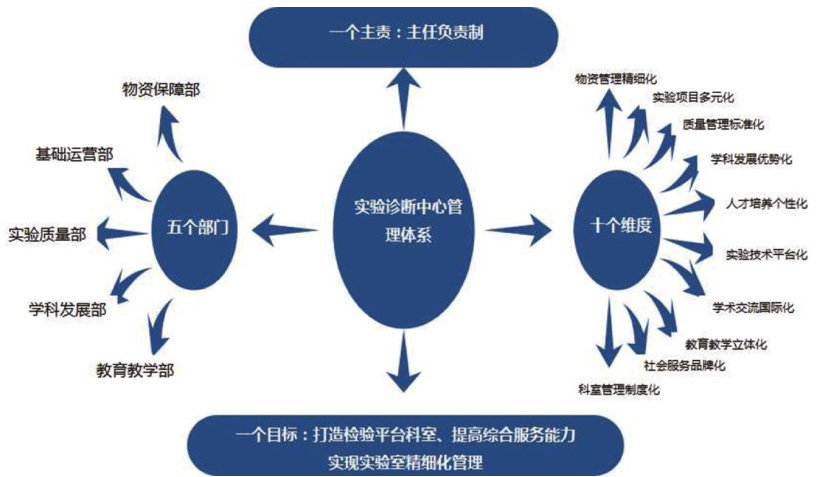

论著·临床研究 | 临床实验室提高突发病原危害管理水平“3+N”体系建立及应用

论著·临床研究 | 临床实验室提高突发病原危害管理水平“3+N”体系建立及应用